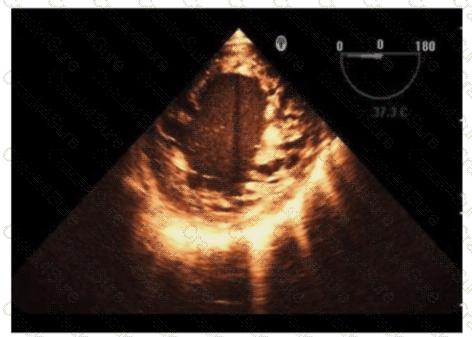

Which technique best determines a trileaflet aortic valve from a bicuspid aortic valve?

Which view is best for assessing atrial situs in the presence of congenital heart disease?